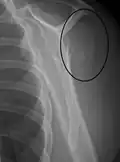

A fracture of the greater tuberosity of the humerus -

Fracture of the greater tuberosity of the humerus -